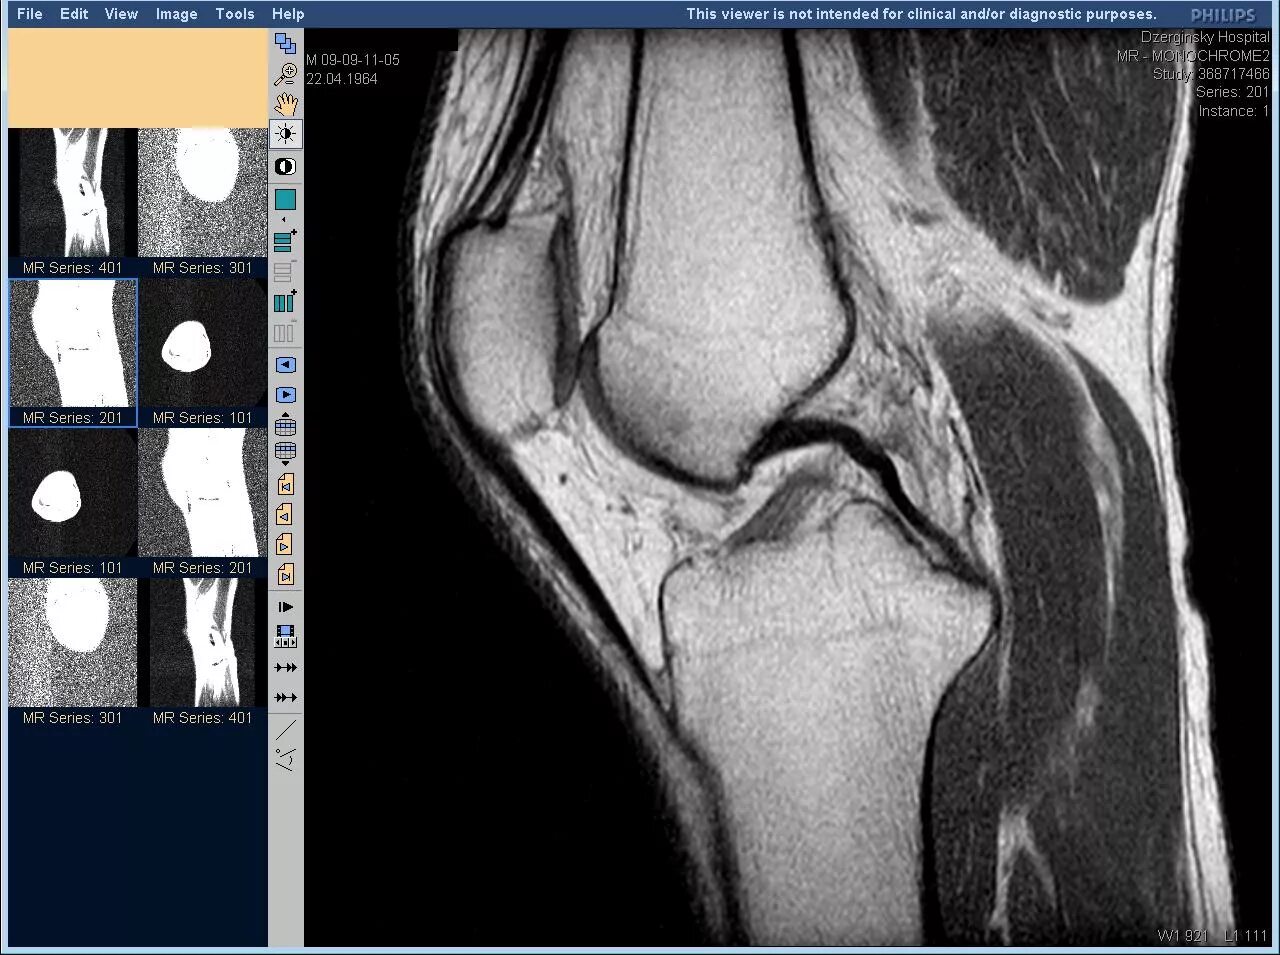

Мрт коленного сустава одежда